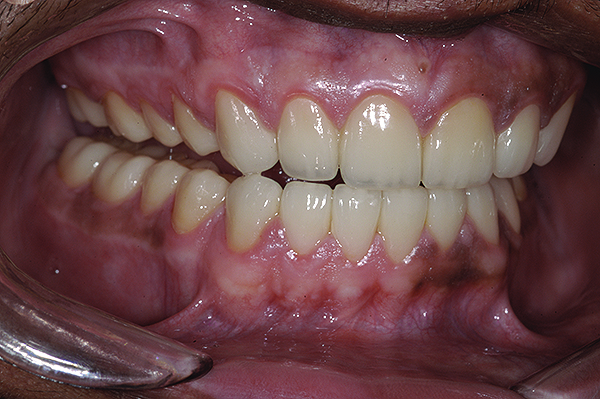

The final restorations depicted restoration of form, function, and beauty, with good harmony of restoration and the periodontium (Figure 19 through Figure 25). MIP was in harmony with CR, and right and left lateral excursion discluded all posteriors with anterior group function. The postoperative orthopantomogram (OPG) (Figure 26) shows the treatment done while maintaining the vitality of anterior teeth.

Figure 20. Postoperative 1:2 retracted frontal view.

Figure 20

Figure 21. Postoperative 1:2 retracted right lateral view.

Figure 21

Figure 22. Postoperative 1:2 retracted left lateral view.

Figure 22

Figure 23. Postoperative 1:1 retracted frontal view.

Figure 23